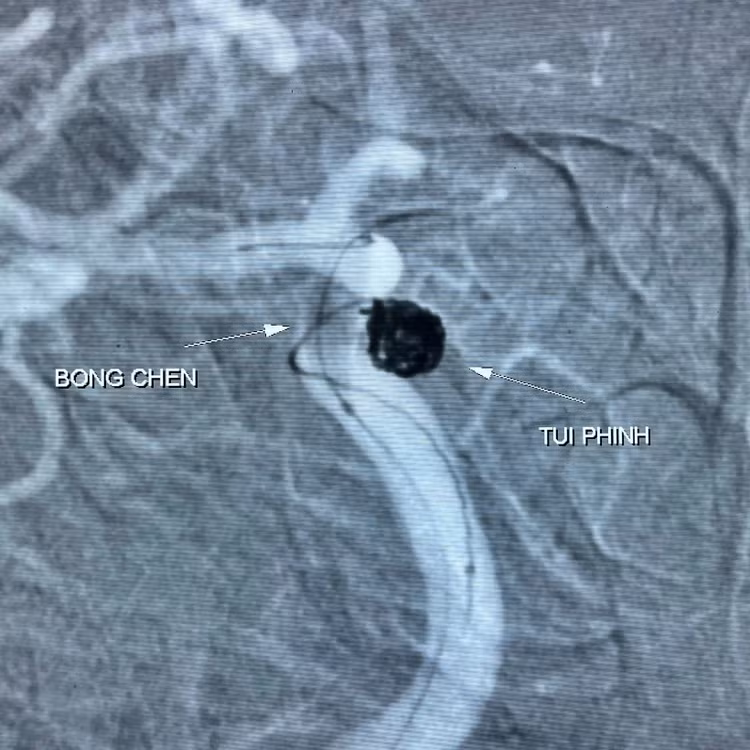

Qua khai thác bệnh nhân có tiền sử khỏe mạnh, không có bệnh lý mạn tính, kết quả chụp cắt lớp mạch não phát hiện túi phình động mạch cảnh trong phải, kích thước 5,2 x 5,4mm, cổ rộng đường kính 4,3mm, không có máu tụ quanh túi phình.

Các bác sĩ hội chẩn đánh giá bệnh nhân có túi phình động mạch cảnh trong phải kích thước lớn cần xử trí can thiệp để tránh nguy cơ vỡ gây đột quỵ xuất huyết não. Túi phình phần cổ rộng sẽ gây khó khăn trong quá trình thả vật liệu nút tắc túi phình (coil) rất dễ trôi ra ngoài và gây tai biến.

Vì vậy, kíp can thiệp quyết định sử dụng phương pháp nút túi phình bằng vòng xoắn kim loại (coil) kết hợp thêm bóng chẹn cổ nhằm tăng hiệu quả can thiệp và đảm bảo an toàn cho người bệnh.

| Túi phình động mạch |

Kíp can thiệp do BS.CKII Ngô Quang Chức – Trưởng khoa Chẩn đoán hình ảnh phụ trách cùng các bác sĩ, kỹ thuật viên trong khoa tiến hành luồn vi ống thông từ động mạch đùi lên đoạn mạch não bị tổn thương, tiếp cận túi phình động mạch não và tiến hành bơm bóng chẹn cổ, tiếp tục thả 4 vòng xoắn kim loại (coil) để nút bít túi phình dưới sự hỗ trợ của hệ thống chụp mạch số hóa xóa nền 2 bình diện (DSA).

Kết quả chụp mạch kiểm tra thấy túi phình cổ rộng đã được bít hoàn toàn, tuần hoàn động mạch não hồi phục trở lại. Bệnh nhân tỉnh táo trong suốt quá trình can thiệp, sức khỏe hồi phục tốt, không đau đớn, đi lại và ăn uống bình thường sau can thiệp 1 ngày.